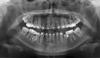

Asymmetry. Hemifacial? Three Years of Treatment Already.

This patient has already had three years of treatment and is missing three bicuspids with one more to be extracted. Is this case headed for surgery?